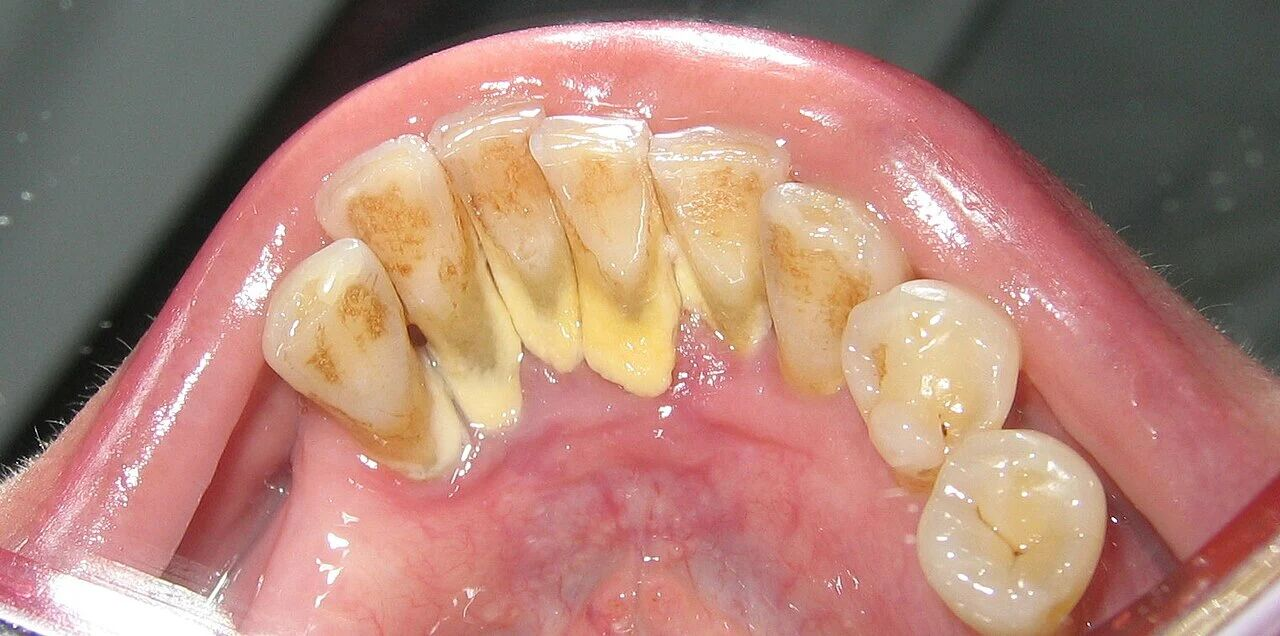

牙齿上的牙结石(牙根处黄色部分)图源:wikipedia

这也解释了为什么牙结石最容易出现在下门牙内侧、上后牙的外侧,这些位置都是唾液腺开口处,矿物质源源不断供应,堪称牙结石的“高产区”。